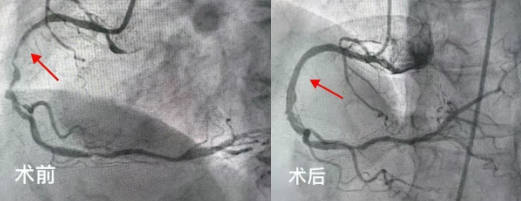

2025年5月,吉林市人民医院心内五病区收治了一位70岁的老年女性患者。该患者反复心绞痛1年,近3天症状加重。入院后,冠脉造影检查明确显示其存在严重的三支血管病变。通常情况下,冠脉搭桥手术是此类患者的首选治疗方案,但家属综合考虑患者年龄和身体状况,最终选择冠脉介入治疗。经心内五病区张金子主任团队审慎评估,决定分两次为患者实施支架植入术。

第一次手术顺利完成,在患者右冠状动脉植入两枚支架,心绞痛症状有所缓解,但仍反复发作。经过两周的精心调整,5月25日,患者再次入院接受第二次支架植入手术。然而,术后返回病区时,患者突发严重并发症——因剧烈恶心呕吐,吐出大量鲜血。由于患者既往有慢性胃炎病史,这一突发状况导致其病情急剧恶化,生命危在旦夕。